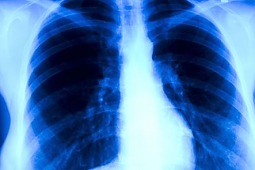

24 marca przypadł Światowy Dzień Walki z Gruźlicą

Gruźlica jest chorobą zakaźną, wywołaną przez prątki kwasooporne z grupy Mycobacterium tuberculosis complex – M. tuberculosis, M. bovis i M.

africanum. Światowy dzień walki z tą chorobą ustanowiono 24 marca w celu upamiętnienia wydarzenia z 1882 roku, kiedy Robert Koch ogłosił swoje odkrycie.Mimo postępu w zmiejszaniu liczby zachorowań, gruźlica jest nadal groźna. Według najnowszego raportu Światowej Organizacji Zdrowia

(WHO) i Europejskiego Centrum Kontroli Chorób (ECDC),w latach 2011-2015 w Europie liczba zachorowań na gruźlicę spadła o 4,3 proc., a liczba zgonów – o 8,5 proc. Jednocześnie o 40 proc. wzrosła liczba przypadków tej choroby u osób z wirusem HIV.